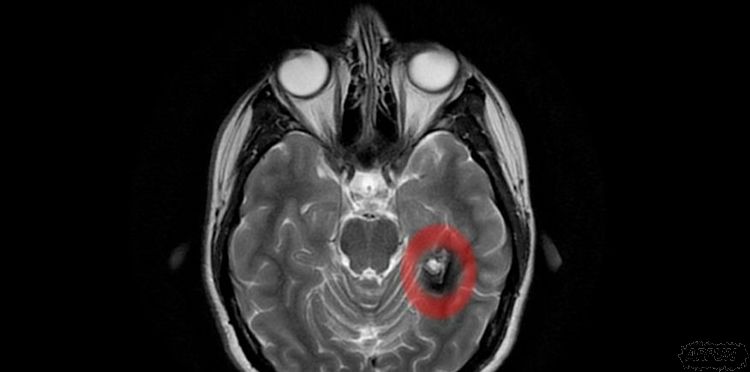

这些研究人员专注在那些背外侧前额叶皮质层(dorsolateral prefrontal cortex, dlPFC)受损的退伍军人。

他们确认出在这些脑部地区病变之间的关系、退伍军人宗教信仰的力量、以及认知的低灵活性。